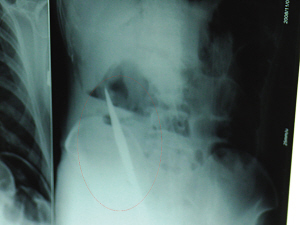

X光片上,尖刀清晰可見。

從男子體內取出的尖刀足足有19厘米長。

6日上午,記者在徐州礦務集團總醫院重癥監護室見到了這名男子,目前他雖然已經恢復了意識,但還不能開口說話,需要呼吸機輔助呼吸。據醫生介紹,4日中午12時左右,這名男子因服毒輕生被緊急送到醫院進行搶救,之前,這名男子已經在當地鄉鎮醫院進行了近20小時的治療,但效果不佳!安∪吮晦D院到礦總院時已神志不清,血壓極低,處于休克狀態!本茸o人員給男子洗胃、初步處理以后,發現男子呼吸急促,于是趕緊給他拍片檢查。結果讓所有的醫生大吃一驚,竟有一把尖狀異物橫在該男子腹腔內!當天下午5時30分,輕生男子被推上了手術臺。經過40多分鐘的手術,該男子腹腔被打開,手術醫生發現,男子體內的金屬狀異物竟然是一把長19厘米的尖刀!

醫生告訴記者,手術后,醫生在病人身上并未發現刀痕,最后,經過檢查發現,在該男子直腸處找到穿孔。醫生從醫學角度分析后認為,這把尖刀應該是從肛門插入直腸的。醫生說,因為病人搶救及時,尖刀并未傷及要害,所以暫時保住了性命,但后期可能會出現腹腔感染、AIDS、器官衰竭等多種并發癥。